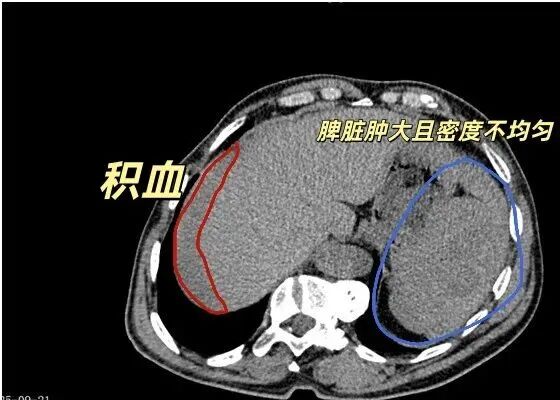

张大叔到院后,急诊绿色通道迅速启动。CT检查提示:脾脏破裂可能、腹腔及盆腔积血,脊柱侧弯,右侧肋骨骨皮质扭曲。报告为手术方案提供了关键依据。此时张大叔已陷入失血性休克,胃肠外科张志宇主任团队立即为其行全脾切除术。术中发现腹腔积血与脾周血凝块总计约2300ml,脾脏上极有4cm裂口并活动性出血,周围网膜部分粘连,其他脏器未见损伤。为应对大量出血,手术采用自体血回输技术,将术中出血经处理转化为纯净红细胞回输患者体内,共回输1624ml,有效维持了循环稳定,减少了对异体输血的需求。手术团队精准处理脾血管,顺利切除脾脏。此次救治通过影像精准诊断、自体血回输和外科精细操作,实现多环节高效衔接,体现了医院在危重症救治方面的综合实力。